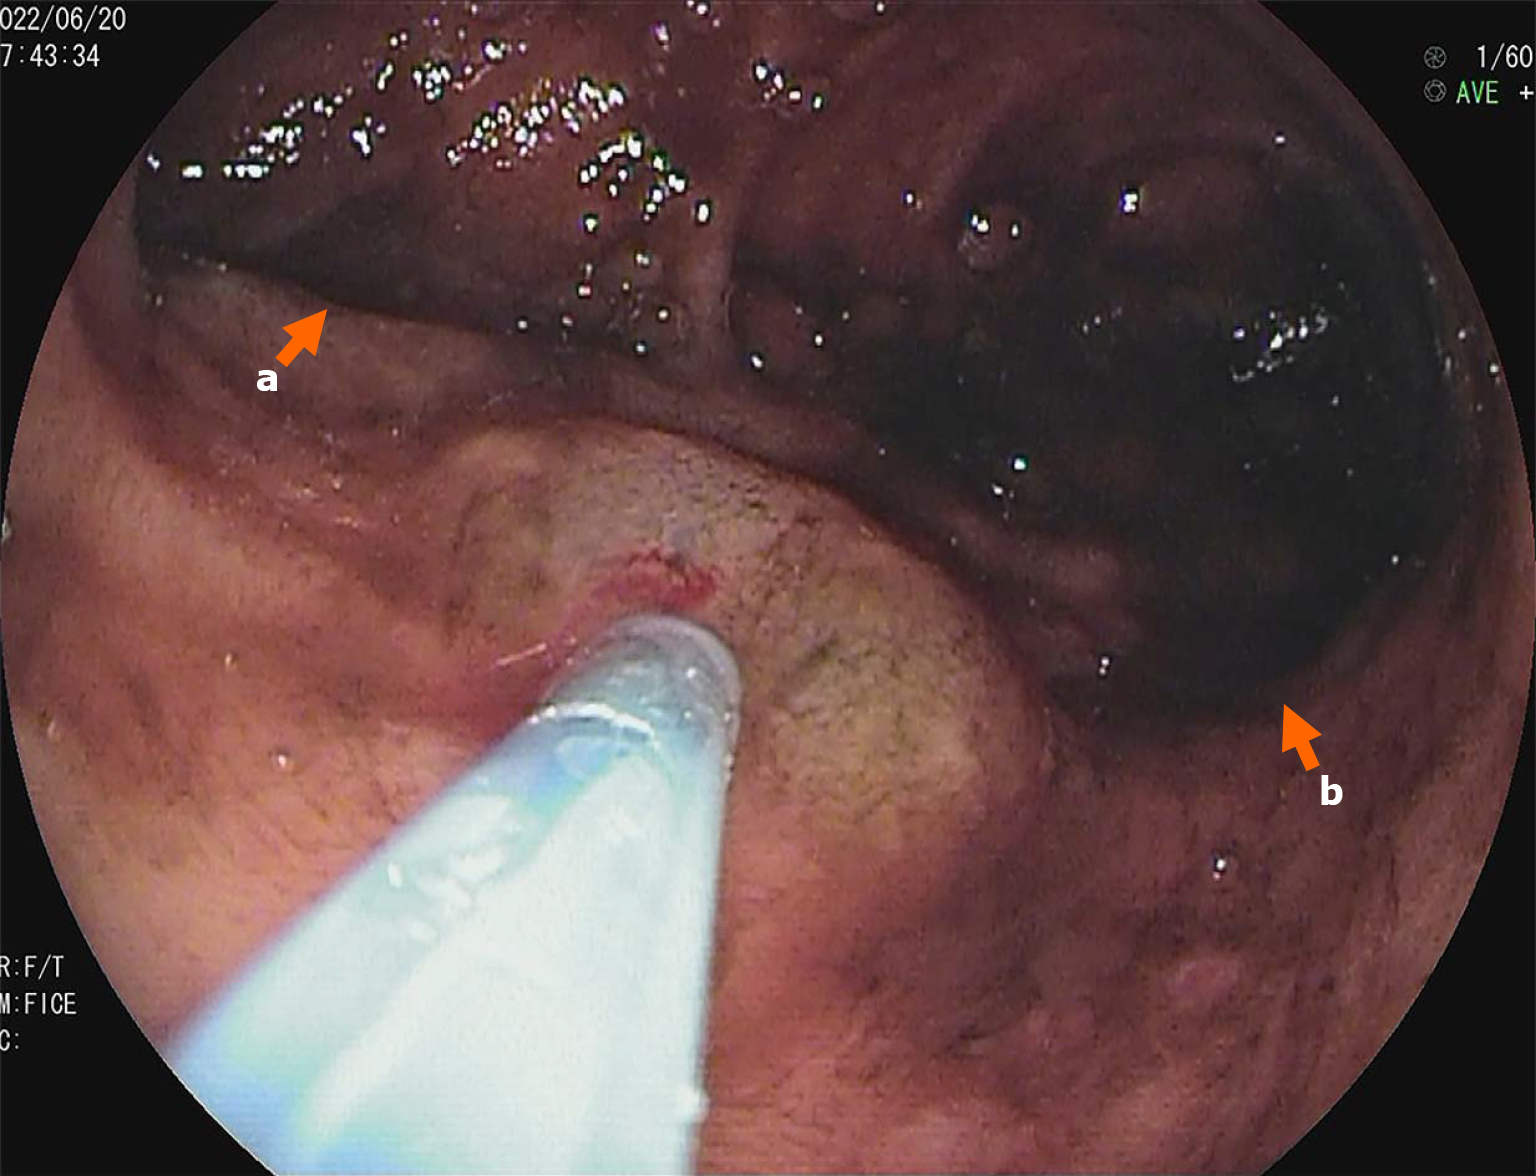

The Meckel scan: After injection of the radiotracer (99mTcO4-), gastric imaging was performed. An abnormal tracer concentration was observed in the mid-abdomen, which appeared as a round lesion. Over time, the tracer concentration increased slightly; however, there were no significant changes in shape or location (Figure 1). Examination conclusion: Positive imaging of ectopic gastric mucosa. Based on this, DBE was performed, and a mucosal protrusion was identified 60 cm proximal to the ileocecal valve, presenting with a “double lumen sign” (Figure 2). The distal lumen had normal ileal mucosa, whereas the proximal lumen had a circumferential ulcerated stricture occupying 75% of the bowel circumference, with exudate. The ulcer bed had raised bordering mucosa, contact hemorrhage, and a firm texture. After biopsy, the lesion was marked with India ink. Histopathological examination confirmed ileal adenocarcinoma (Figure 3) with mismatch repair proficiency (MutL homolog 1+, MutS homolog 2+, MutS homolog 6+, and postmeiotic segregation increased 2+).